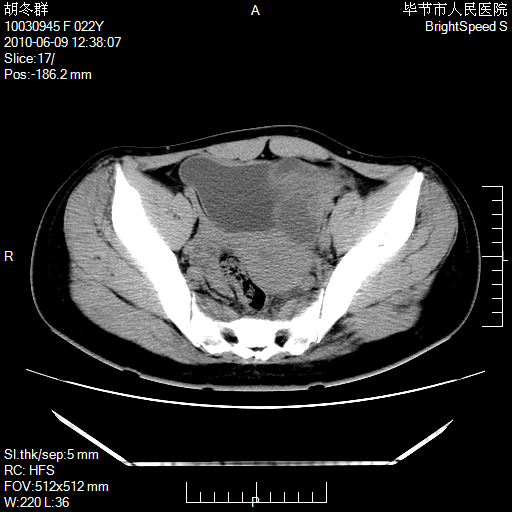

患者23岁,发现腹部包块3月。

盆腔内囊性占位;穿刺或者直接手术拿掉即可,不必紧张。

盆腔内囊性占位性病变;考虑左侧卵巢囊腺瘤。

有分隔、壁薄,支持考虑左侧卵巢囊腺瘤。

左侧卵巢浆液性囊腺瘤。

有分隔、壁薄,支持考虑左侧卵巢囊腺瘤。排尿后,膀胱缩小,由于重力作用,肿块下移就到了膀胱位置,很好理解。